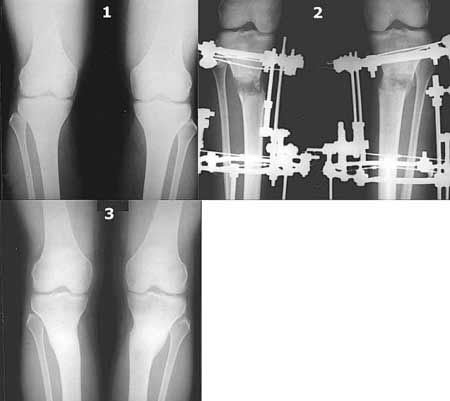

AC> Вот, с учетом и без учета, и на разных уровнях...

Из приведнной схемы не совсеим понял что означают разноцветные линии.

И зачем латерализация периферического фрагмента. Я всегда делаю медиализацию. См схему. И для данного случая медиализация подходит как нельзя лучше.

Черные - это нынешняя механическая ось. Красные - это планируемая правильная ось.

a> Я всегда делаю медиализацию. См схему. И для данного случая

Медиализация - это чисто эстетический прием, как я понимаю. Поскольку если делать остеотомию ниже вершины деформации, для восстановления оси надо делать смещение по ширине, в данном случае как раз латерализацию.

А вот на схемке без осей - там на разных уровнях (который правильнее?) устранение варуса чисто открытым клином без медиализации-латерализации. Если как-то так сделать - этого недостаточно будет?

Картинки - в приложении.Будут вопросы - готов ответить.

Ещё картинка - схема. Хотя у Соломина всё написано.